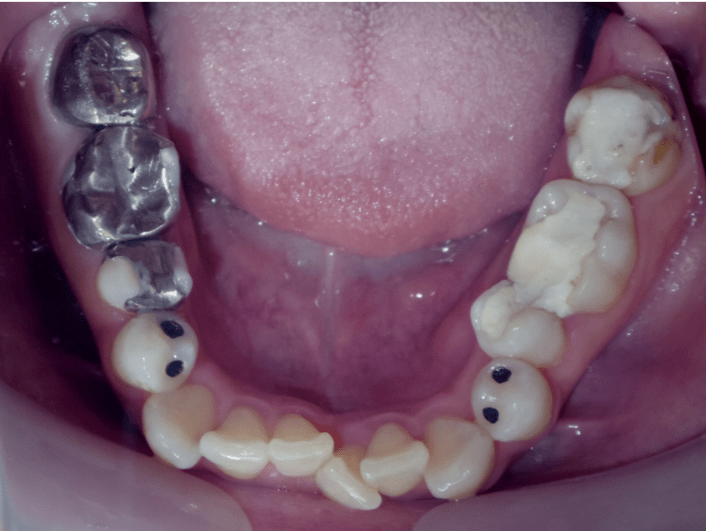

八重歯、捻転歯

BEFORE

上下の軽度の叢生があり、上顎に内側に大きく入り込んだ歯牙がある。補綴が多く、IPRでスペースを確保できるのでインビザラインでの治療が可能と判断した。

外して影響の少ない補綴は矯正前に外して、矯正後に再度やりなした。

年齢/性別

39歳 女性

主訴

上下の歯並びがガタガタと奥歯の噛み合わせ。銀歯をやり替えたい。

リスク

叢生の改善時に歯肉の退縮が起こる

費用

85万円(矯正費用)

期間

2 6 ヶ月